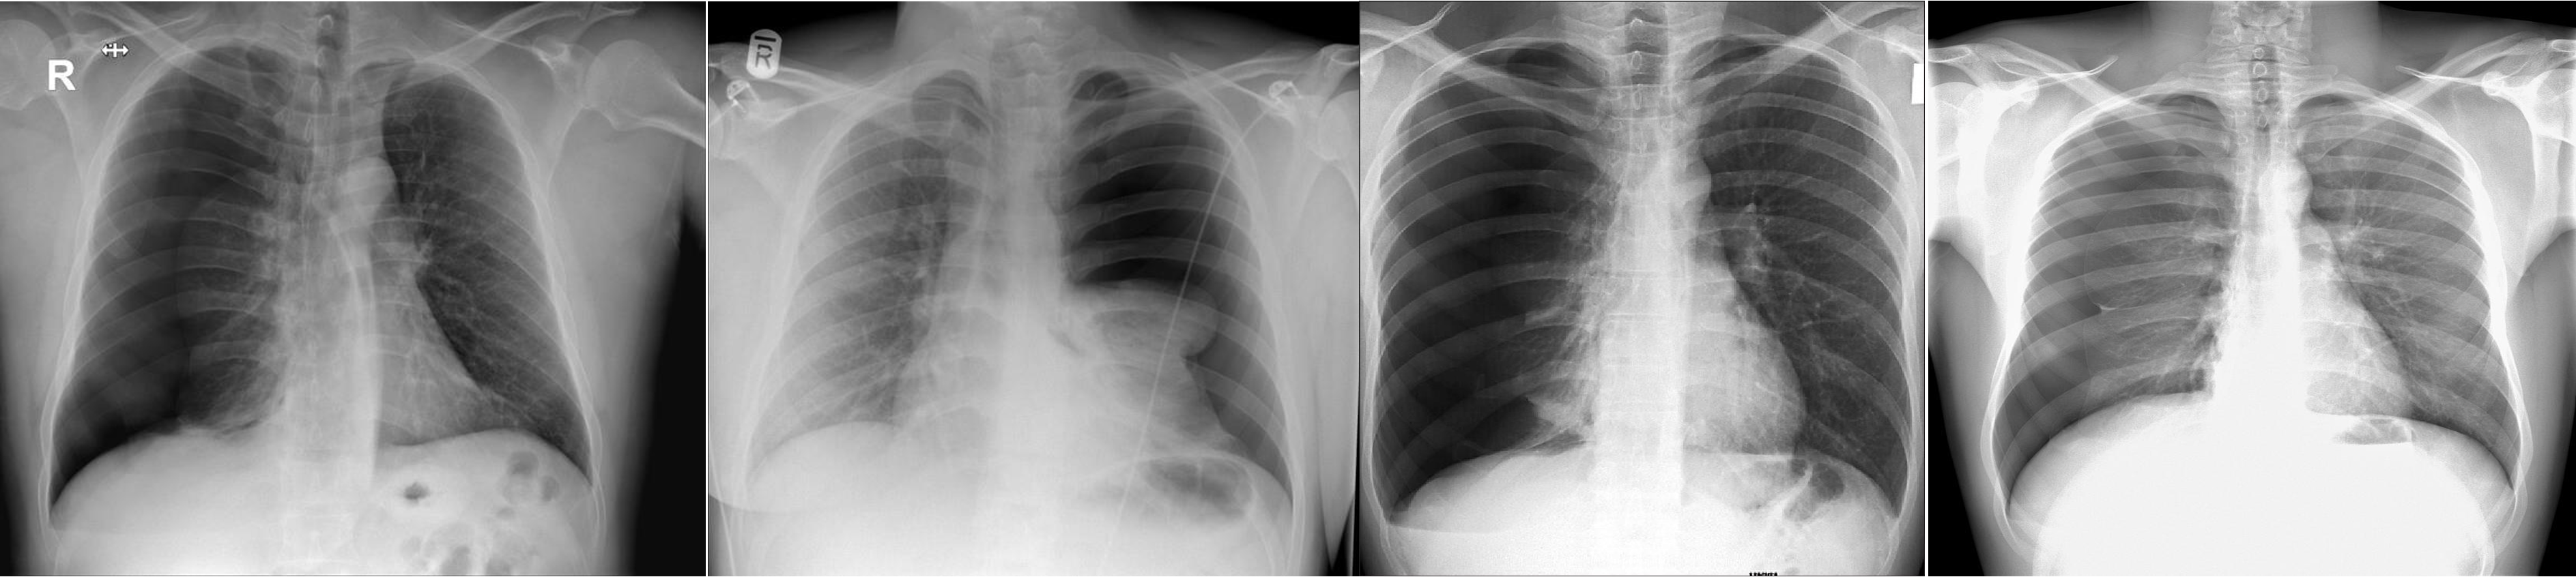

Chest Imaging

- Pneumothorax - Right lung

- Pneumothorax - Left lung - mediastinum pushed

- Pneumothorax - RT